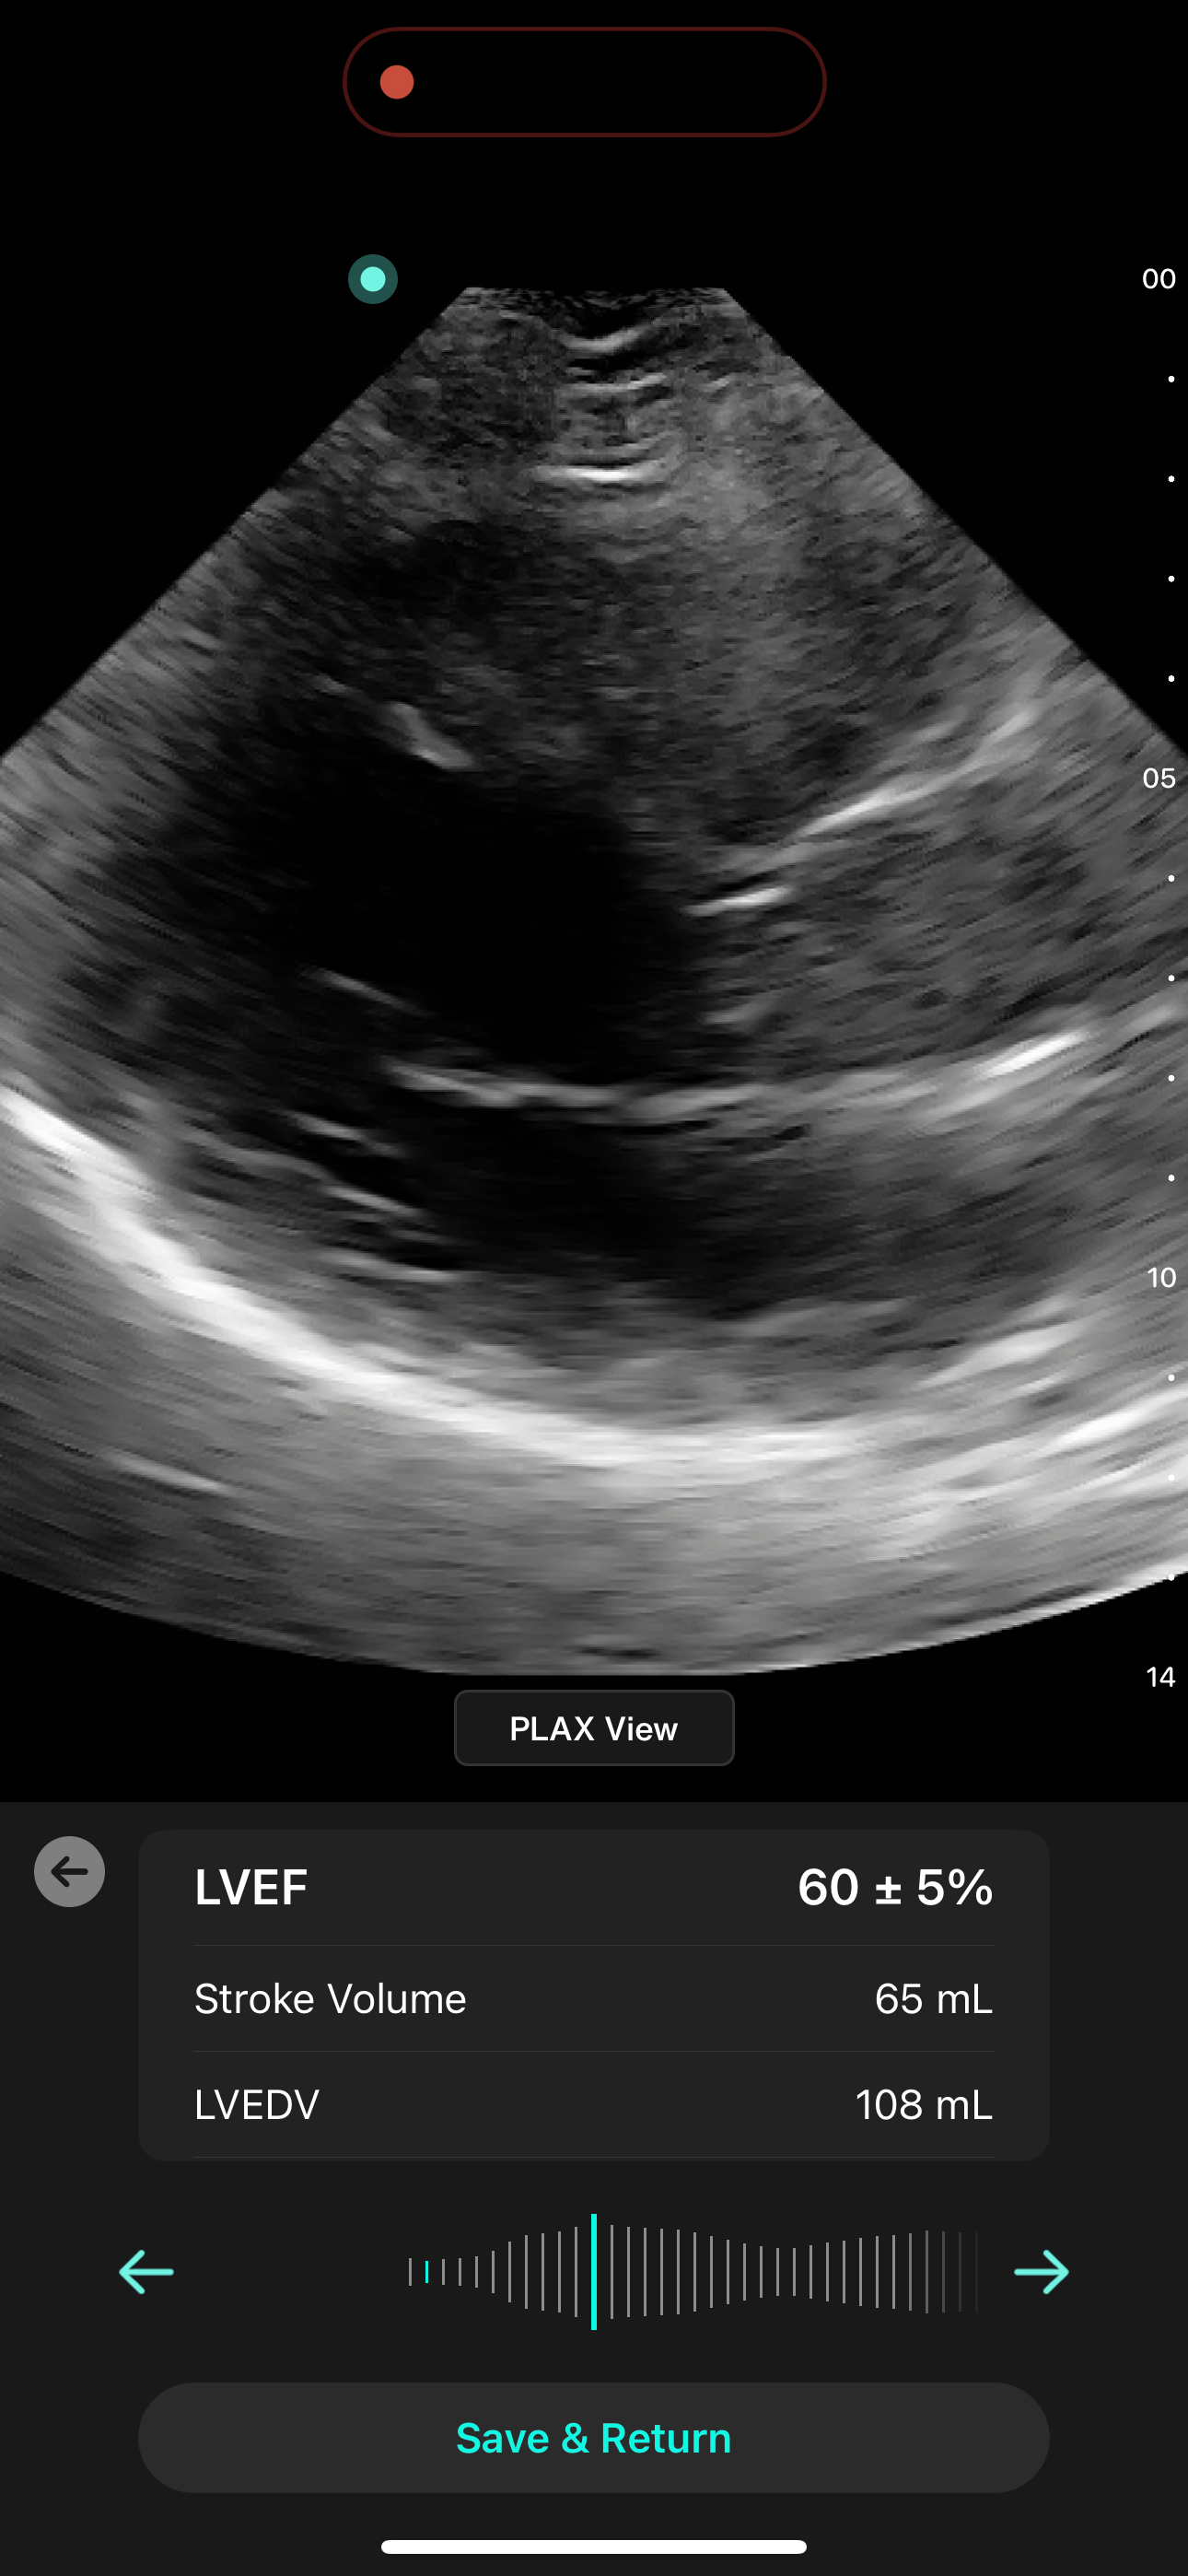

Cardiac AI

With Exo’s Cardiac AI, you can measure left ventricular ejection fraction (LVEF) and stroke volume in a few heartbeats in both parasternal long axis (PLAX) and apical four-chamber (A4C) views, making it easier than ever for POCUS users to get to answers.